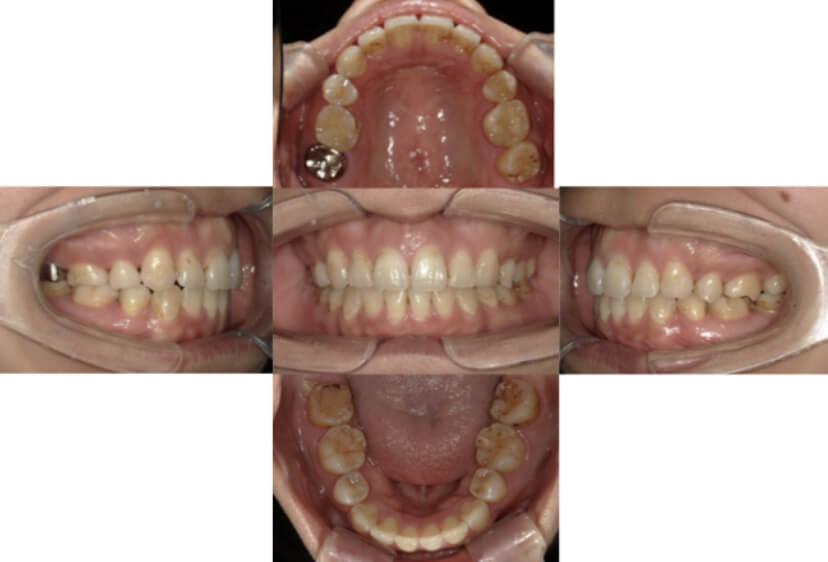

BEFORE

AFTER

上下顎叢生、反対咬合(上下の前歯のガタガタ、若干受け口)のケースです。

装置はラビアル(上下表側)で、上下顎の小臼歯を4本抜歯を行っています。抜歯したスペースを使って、上下の叢生改善と前歯の受け口の改善を行っています。

主訴 前歯のガタガタを治したい。

年齢・性別 45歳 女性

お住まいの地域 神奈川県川崎市

治療方針 抜歯スペースを利用して上前歯の叢生(ガタガタ)の改善と受け口の改善

抜歯部位 上顎左右第一小臼歯、下顎左右第二小臼歯

使用装置 ラビアル(上下表側)、顎間ゴム

治療期間 2年6か月

治療回数 20回

リテーナー クリアリテーナー